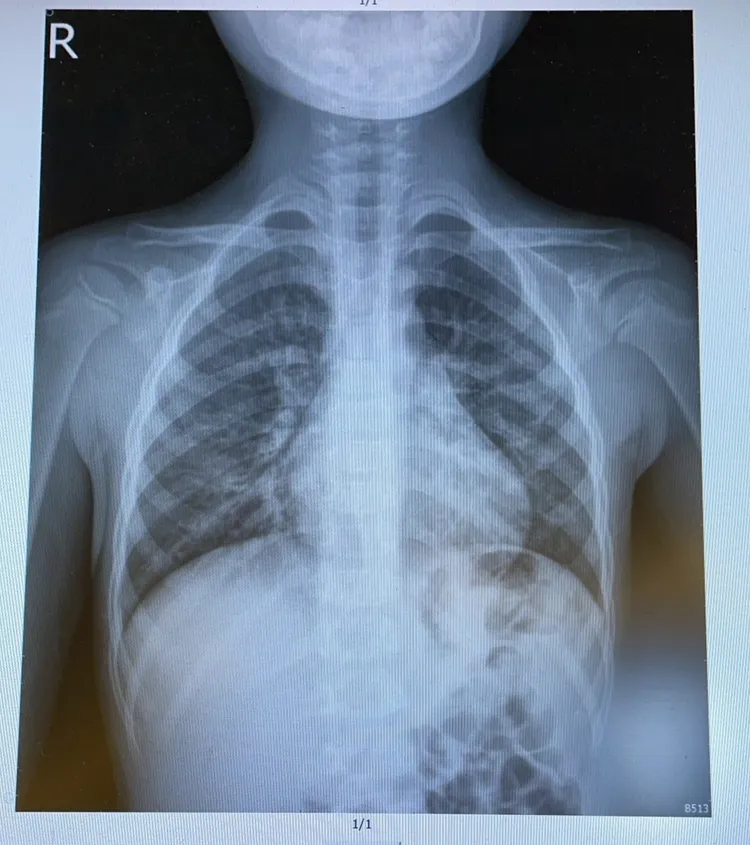

林智葳表示,孩子高燒第1天時,父母會很緊張。高燒第3天時,換成他有點焦慮,燒到第5天時,他請父母無論如何都要去醫院進行檢查。「結果出來,X光片呈現肺炎,微生物證據為hMPV(人類間質肺炎病毒)。」

林智葳表示,雖然hMPV沒有特定的抗病毒藥物可以治療,也不容易引發重症,可是它容易讓孩子高燒數日,有些甚至到第7天才退燒,甚至引發肺炎的特性還是不容忽視。